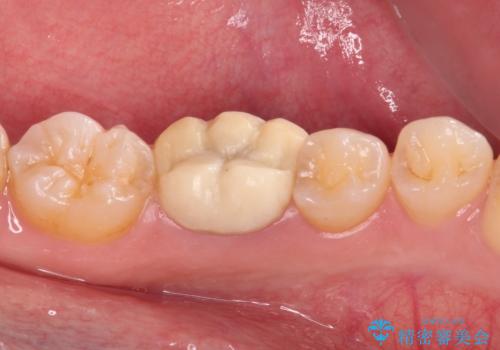

仮歯は見た目は白くても、粘着性の食事がこびりついたり、舌感がざらついていたりと、不快感を感じるだけでなく、長期装着するとむし歯が進行するリスクが高まります。

フルジルコニアクラウンを装着したことにより、舌感が改善されるとともに、むし歯再発リスクを軽減することができました。